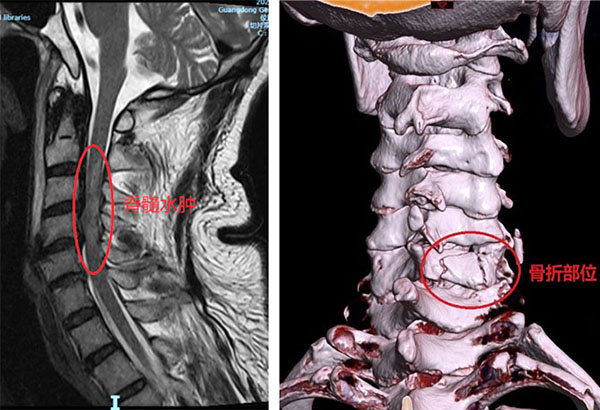

我院脊柱外科陈崇医师在急诊了解详细病情后,发现患者颈脊髓水肿已至颈3平面,脊髓功随时可能继续恶化,如此情况会危及患者生命。急诊科、放射科、检验科开通生命通道,火速完善检验、检测,同时稳定脊髓水肿情况。昌耘冰主任组织科室会诊,本着快速挽救脊髓功能的职业素养和人文情怀,认为患者脊髓损伤从影像学表现看,未发现脊髓横断性损伤,急诊手术或许是患者脊髓功能挽回的必要手段之一。恰逢次日广州疫情小面积波动,患者又遇到中枢性高热、坠积性肺炎情况,发热门诊完善快速流行病学调查及核酸检测后,医院第一时间启动疫情防控应急预案,高效应对突发状况,快速收入脊柱外科病区,快速完善术前准备。